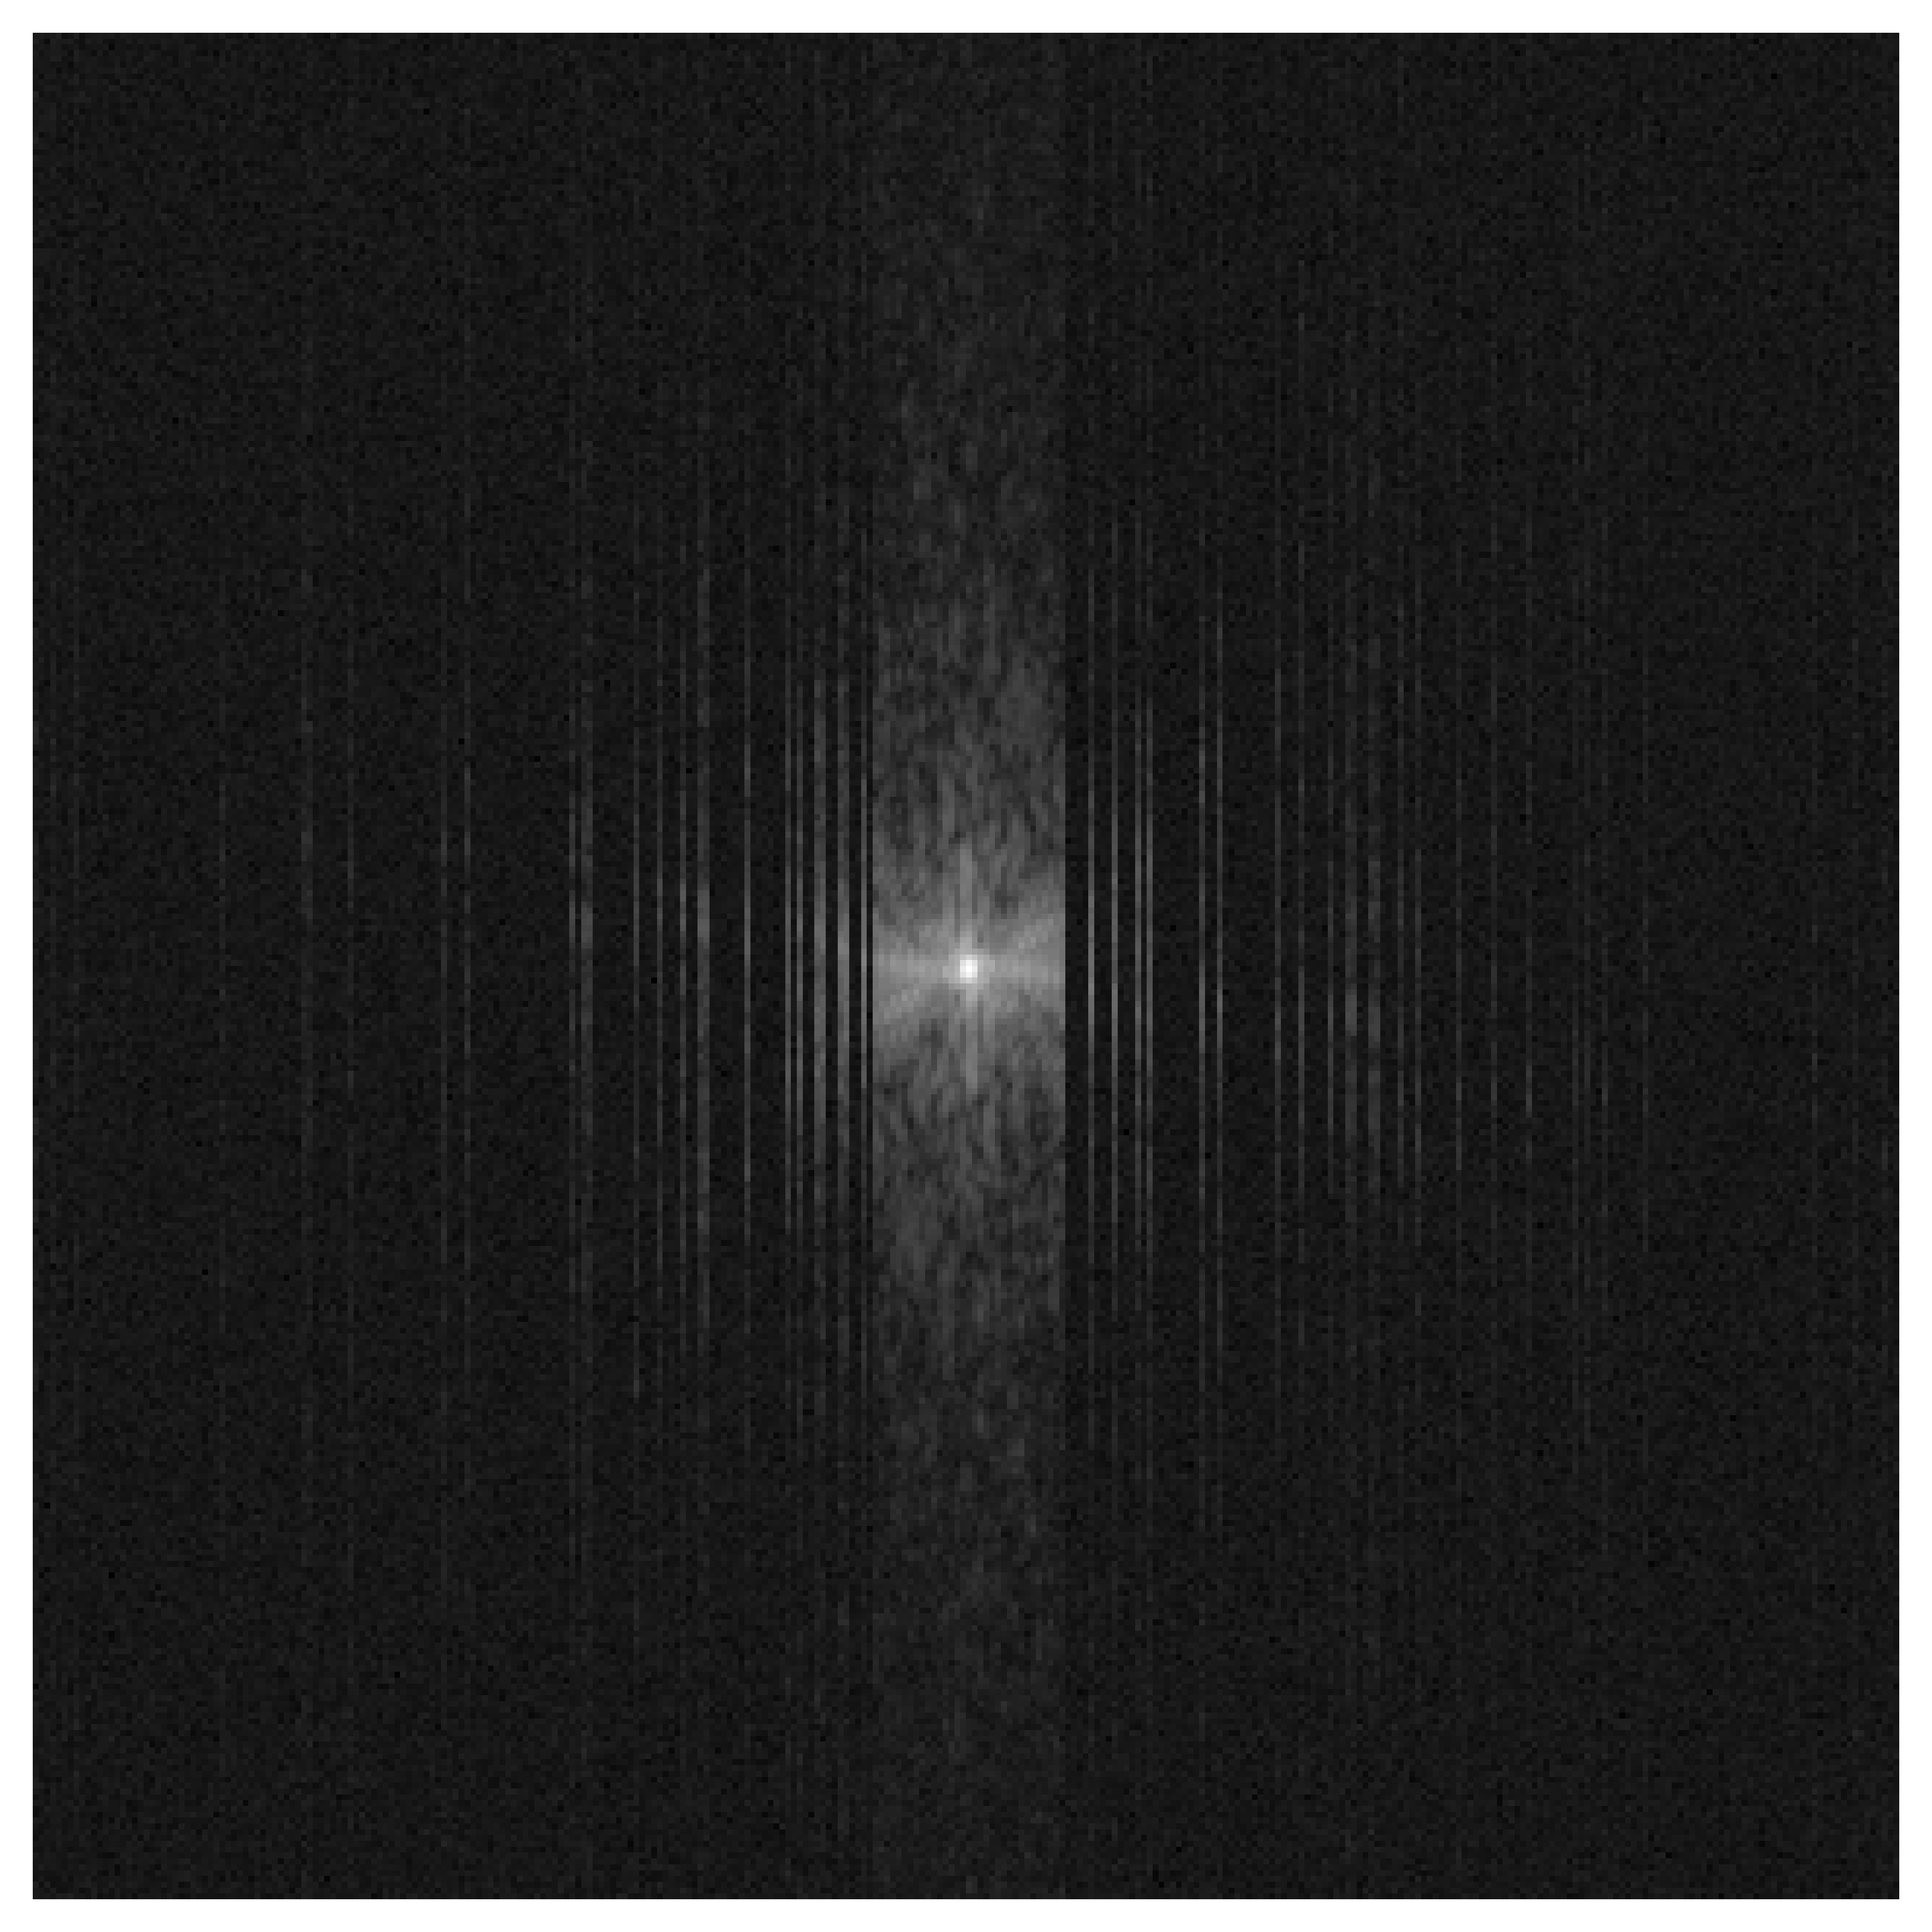

3.4.1 Classical Subsampling Sketch

Classical sketching reduces the number of receiver coils by applying a randomly generated block-selection matrix

𝐒Mcd×Ncd,Mc<Nc.\mathbf{S}\in\mathbb{R}^{M_{c}d\,\times\,N_{c}d},\qquad M_{c}<N_{c}.

The sketched forward model is then

𝐤s=𝐌s𝐅s(𝐒𝐂𝐱),\mathbf{k}^{s}=\mathbf{M}_{s}\,\mathbf{F}_{s}\big(\mathbf{S}\mathbf{C}\mathbf{x}\big),

where 𝐂Ncd×d\mathbf{C}\in\mathbb{C}^{N_{c}d\times d} is the coil-sensitivity operator and 𝐒\mathbf{S} selects McM_{c} coils out of the total NcN_{c} coils. The matrix 𝐒\mathbf{S} is a block-binary matrix composed of d×dd\times d blocks:

𝐒=[𝐒11𝐒1Nc𝐒Mc1𝐒McNc],𝐒ij{𝟎,𝐈d},\mathbf{S}=\begin{bmatrix}\mathbf{S}_{11}&\cdots&\mathbf{S}_{1N_{c}}\\ \vdots&\ddots&\vdots\\ \mathbf{S}_{M_{c}1}&\cdots&\mathbf{S}_{M_{c}N_{c}}\end{bmatrix},\qquad\mathbf{S}_{ij}\in\{\mathbf{0},\mathbf{I}_{d}\},

where 𝟎\mathbf{0} is the d×dd\times d zero matrix and 𝐈d\mathbf{I}_{d} is the d×dd\times d identity matrix. Each row block of 𝐒\mathbf{S} contains exactly one identity block, so that 𝐒\mathbf{S} selects exactly McM_{c} coils from the NcN_{c} available coils. Figure 1 illustrates the concept of classical sketching. Hence one option for us is to apply SkEI directly on multicoil MRI via sweeping through the subsampling sketches. However we found that there is room for improvement for SkEI in this task, and next we are going to present a tailored variant of SkEI for multicoil MRI, namely the C-SkEI, utilizing coil-sketching Oscanoa2024Coil for a refined dimensionality reduction.

Refer to caption

Figure 1: Structured sketching matrix of Oscanoa2024Coil . The classical sketching matrix consists of a group binary mask, with each element being an all-ones matrix or an all-zeros matrix. Each row features exactly an all-ones matrix, and the remaining elements are all-zeros matrices. The coil sketching matrix, in contrast, comprises two blocks: one block is a group identity matrix (not shown in the figure), and the other block follows a group Rademacher distribution with probability p=0.5p=0.5 as showed in the figure.